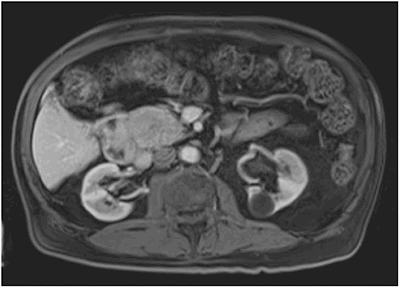

On retrospective review of preoperative imaging, the C-loop of the duodenum did not traverse the midline posterior to the superior mesenteric vessels with the small bowel on the right side of the abdomen (Figure 2). Despite multiple reviews of the preoperative imaging at a multidisciplinary tumor conference and in clinic, the malrotation was not noted. As this is uncommon and unexpected, it was unnoticed, highlighting the biases in the way physicians think.

Figure 2: Preoperative imaging showing C-loop of the duodenum not traversing the midline posterior to the superior mesenteric vessels leaving the small bowel on the right side of the abdomen.